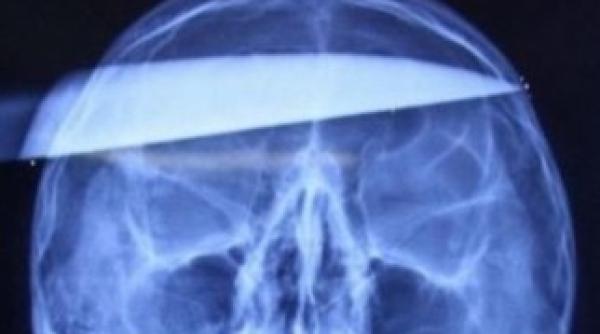

Publicat pe 23 Feb 2014 Un medic și-a obligat pacientul să ia o pastilă. Au urmat clipe de neimaginat